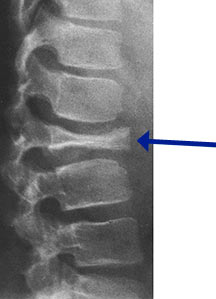

- May arise from any bone and any site within a bone (epiphyseal, metaphyseal, diaphyseal)

- Radiographically variable appearance: may appear benign (geographic) or malignant (permeative or moth eaten)

- Vertebral plana is braced and observed